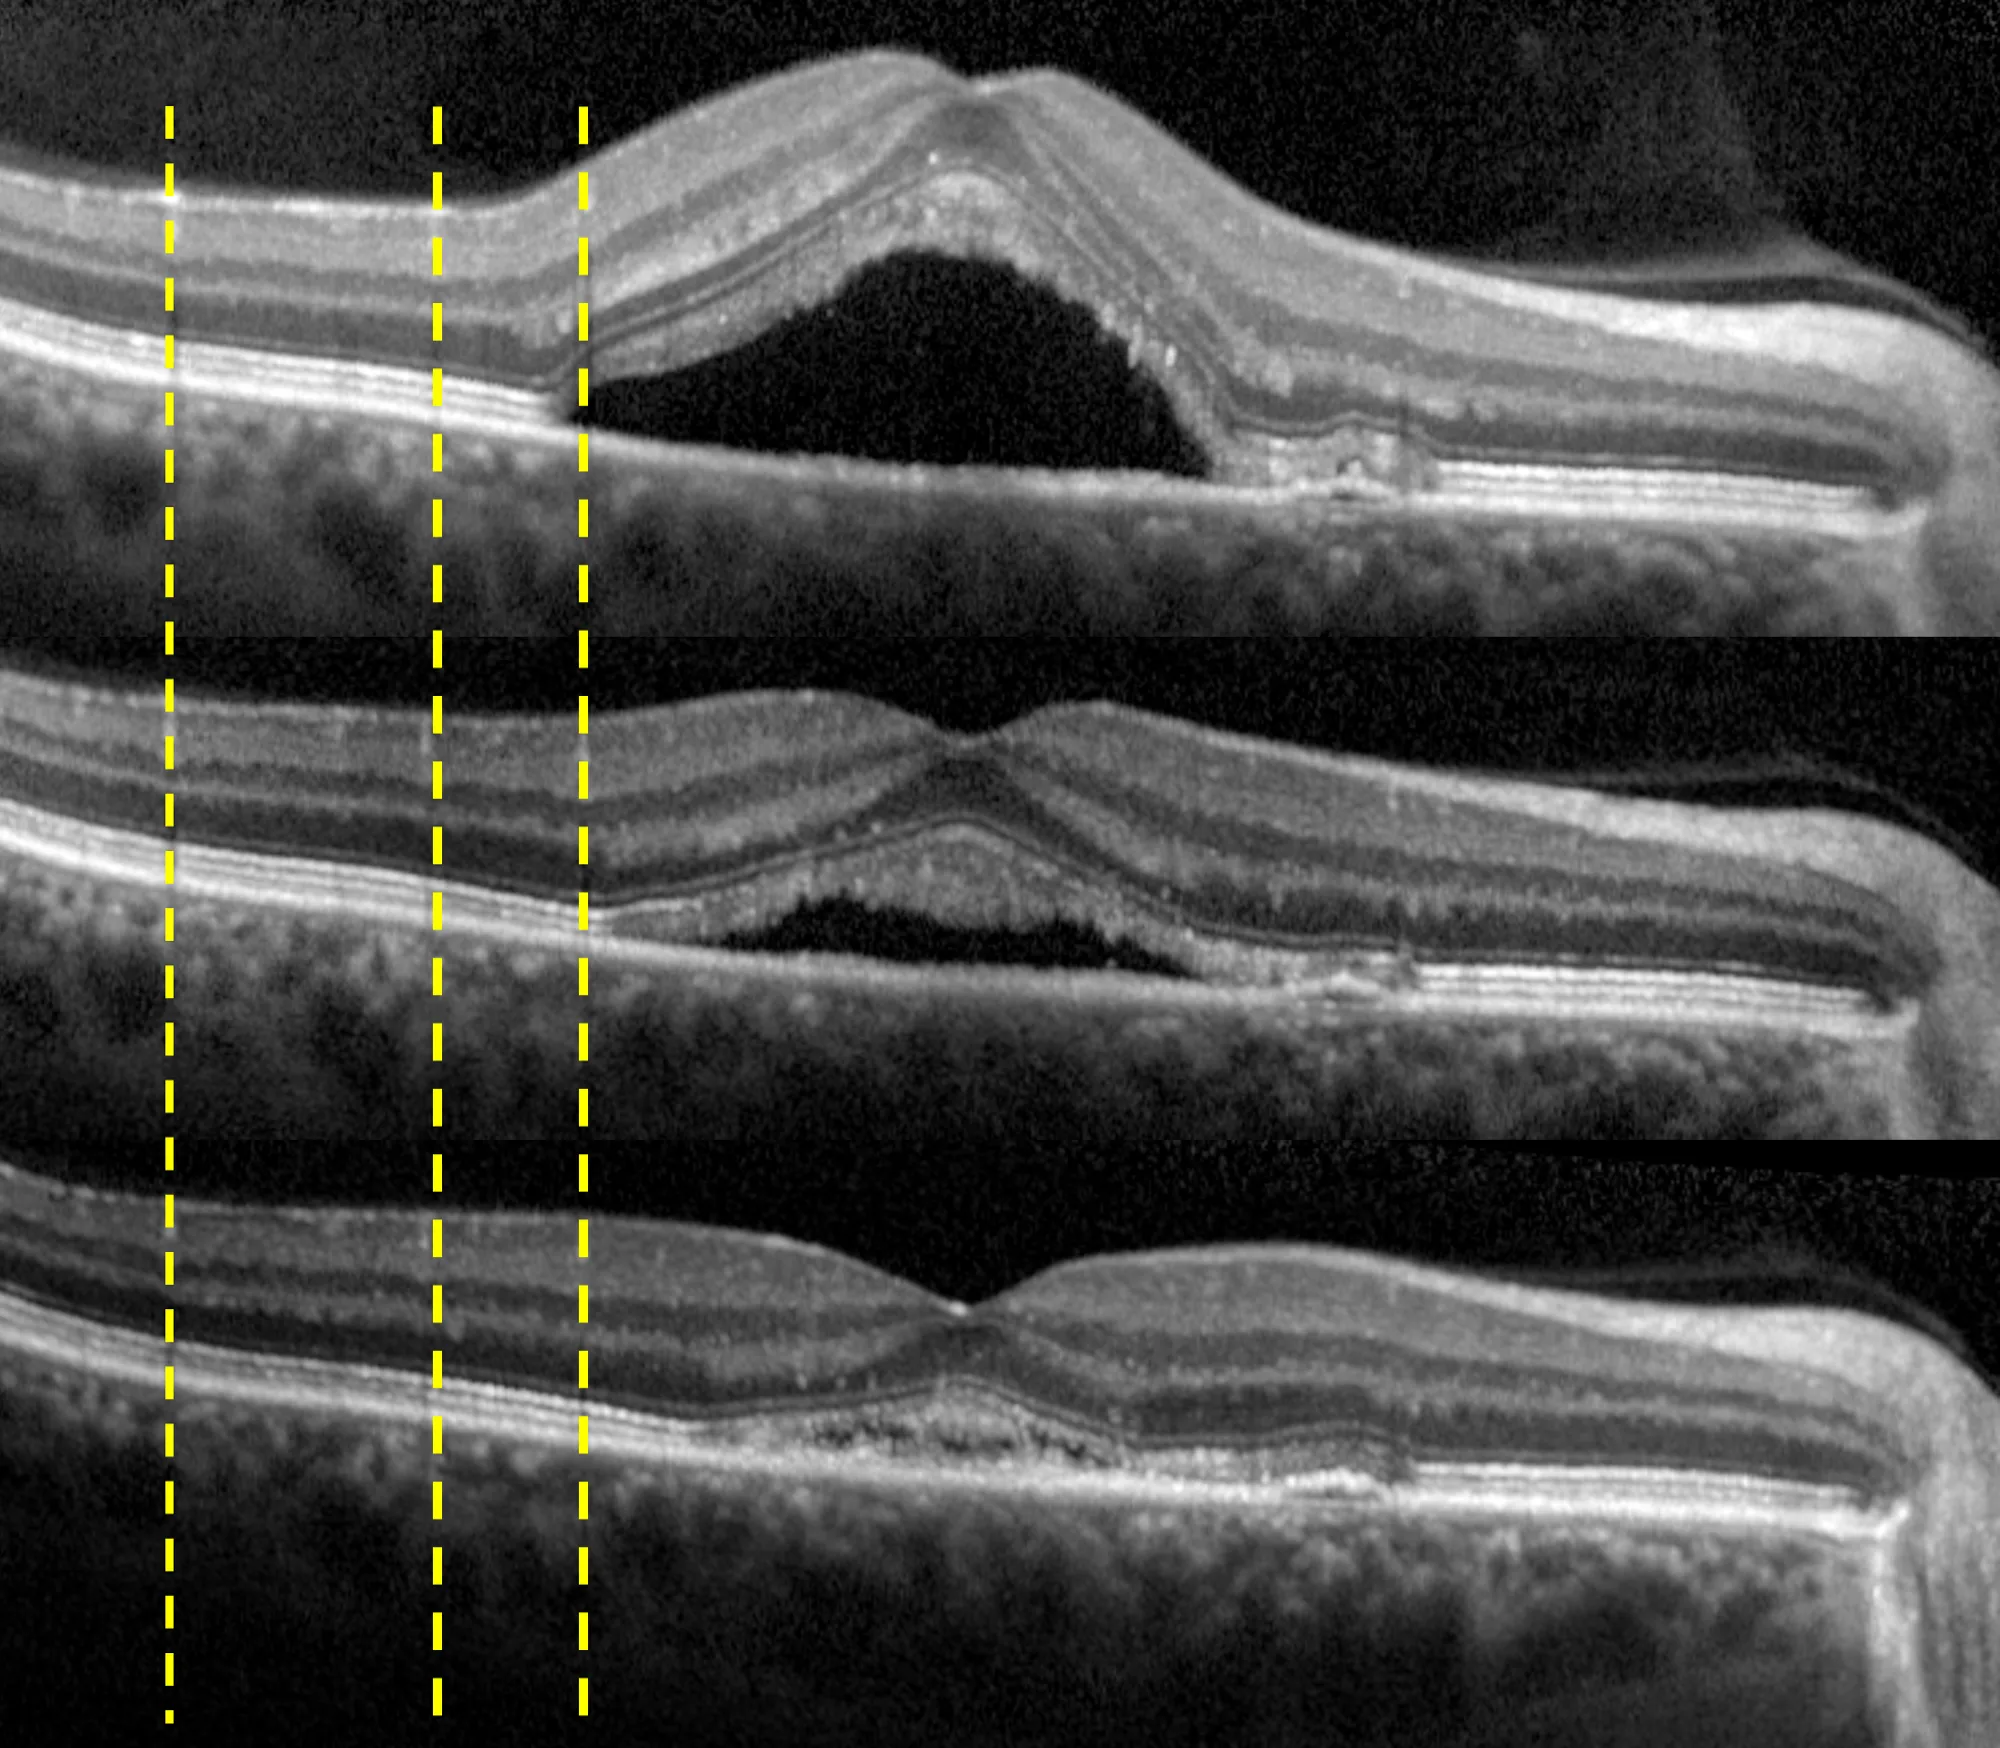

Autorescan

Utilizzando l’immagine del fundus di SPECTRALIS® come mappa di riferimento, AutoRescan posiziona automaticamente le scansioni di follow-up esattamente nella stessa sede anatomica, visita dopo visita.

Un posizionamento accurato e obiettivo è fondamentale per riconoscere anche le più piccole variazioni strutturali — elementi cruciali per la gestione efficace di molte patologie oculari. Studi clinici dimostrano che SPECTRALIS, grazie ad AutoRescan, rileva variazioni dello spessore retinico fino a 1 micron.